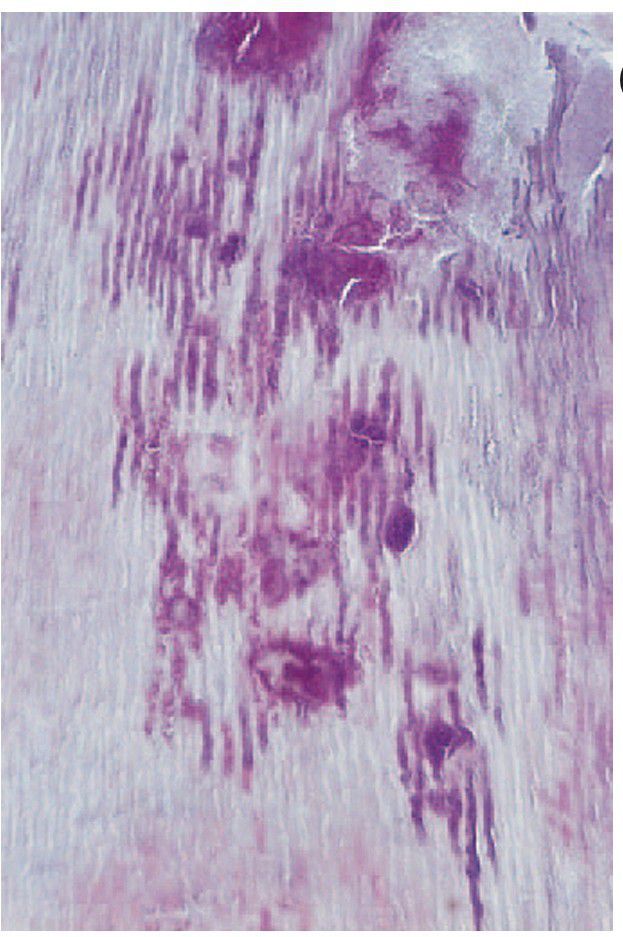

Caries of dentine

Caries of dentine. Infected tubules and fusiform masses of bacteria have expanded into the softened tissue. Adjacent tubules in the demineralised dentine have been bent and pushed aside by these masses.